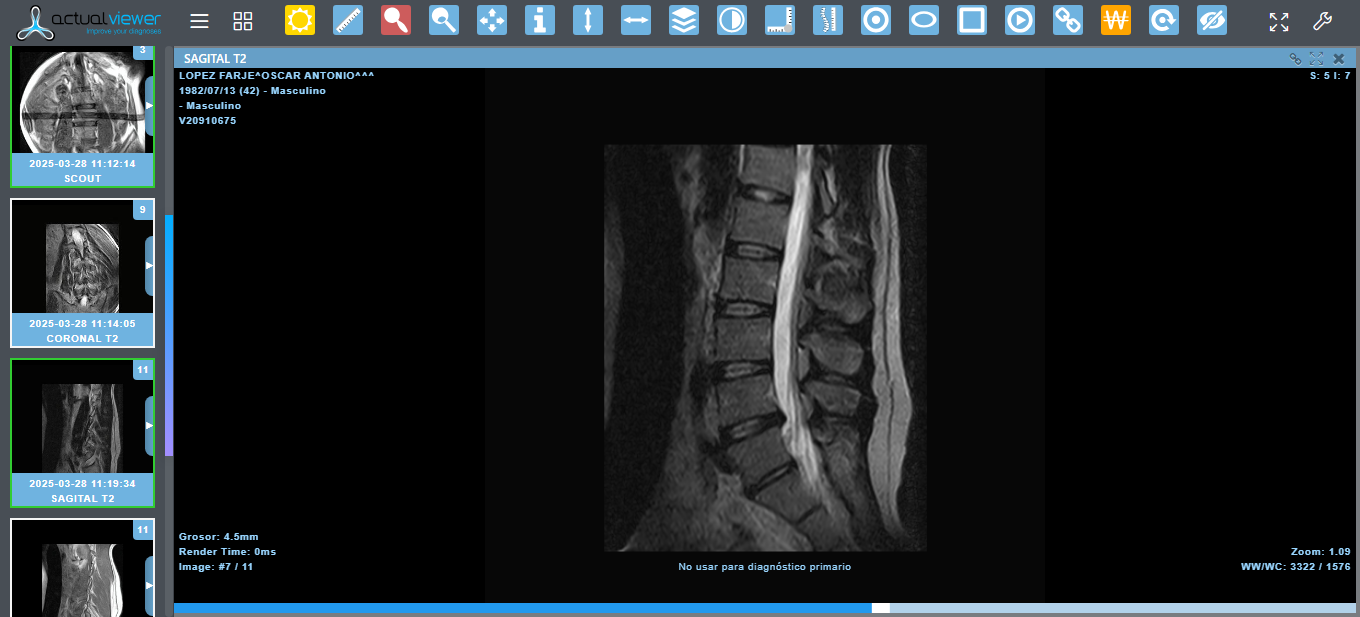

Hello, my name is Oscar. I am 43 years old. I am an orchestral trumpet player, for more than 15 years I was part of the Simon Bolivar Symphony Orchestra, representing Venezuela in thousands of concerts around the world. Today I need your help, due to the economic situation my country is going through, I cannot afford the materials for the arthrodesis I need for my spine surgery. I have been diagnosed with a lumbar disc herniation at the L4-L5 level, accompanied by grade I spondylolisthesis at the L5-S1 level. This has caused severe compression of the lumbar nerve roots, causing constant pain, loss of mobility, and paresthesia. My condition has been evaluated by the medical team, who has indicated the need for imminent spinal surgery.

For several months, I have been suffering from severe lower back pain, which has progressively intensified, radiating to my left lower limb and accompanied by neurological symptoms such as tingling, loss of sensation, and difficulty moving normally.

Furthermore, for a year now, I have been experiencing unexplained urinary symptoms: difficulty initiating urination, a sensation of incomplete emptying, pain and burning, and taking a long time to empty my bladder. After several urological studies, everything points to these symptoms being related to the nerve compression caused by my herniated disc, which increases the urgency of surgery to avoid irreversible damage.